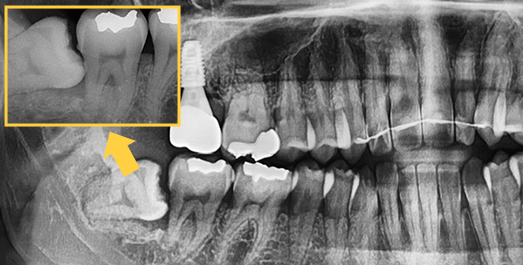

Extraction technique with nerve considerations

Using 3D CT, we evaluate the shape of the wisdom tooth, its roots, and surrounding nerves to support a safer extraction process.

Even advanced cases

can be extracted.

With extensive experience in numerous advanced cases and a wide range of wisdom tooth extractions, you no longer need to go to a university hospital.